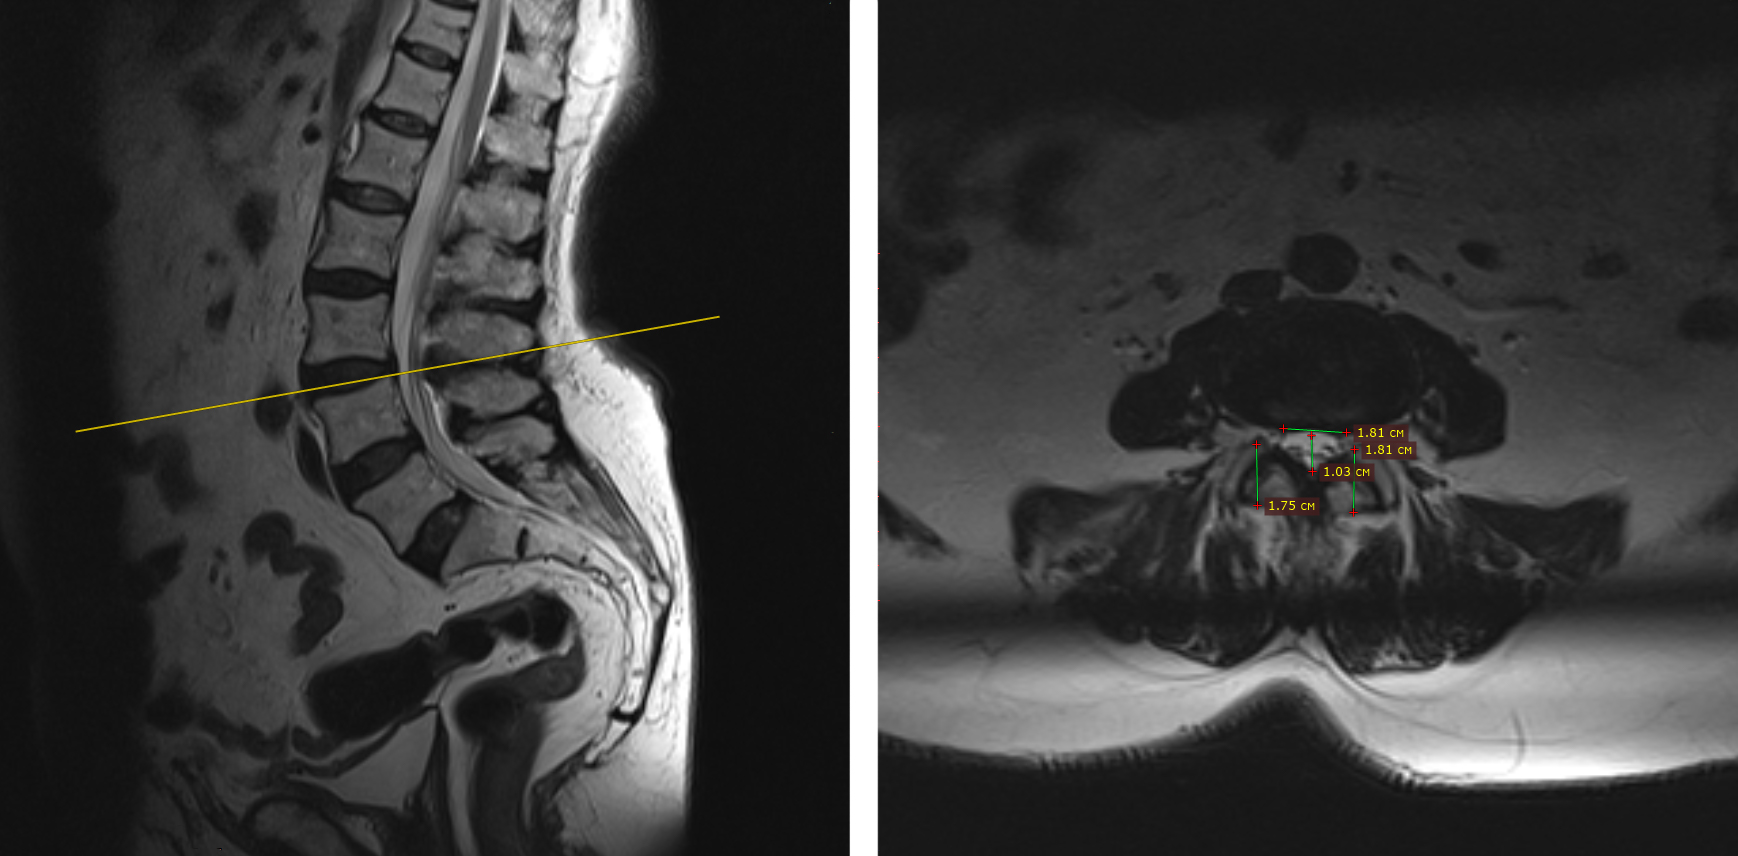

Для подтверждения диагноза пациентка была направлена на МРТ. Исследование показало комплексную картину дегенеративных изменений: протрузии в шейном и поясничном отделах, воспаление фасеточных суставов и стеноз позвоночного канала в пояснице - сужение канала, которое и вызывало слабость в ногах и боли при ходьбе.

На МРТ чётко видны протрузии и сужение позвоночного канала в пояснице